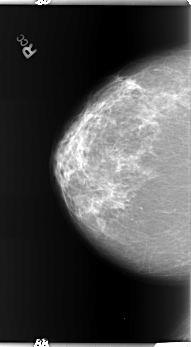

B_3367_1.LEFT_MLO

LEFT_MLO LINES 5904 PIXELS_PER_LINE 3168 BITS_PER_PIXEL 12 RESOLUTION 50 OVERLAY